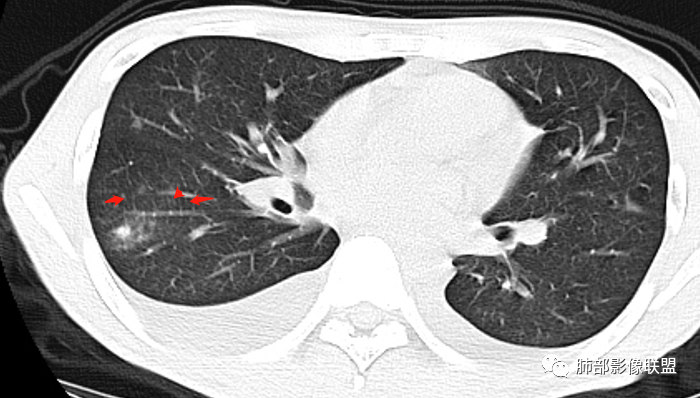

红星:病史资料:患者男,30岁,因“双小腿及双踝双足浮肿1周”入院。患者1周前无明显诱因下感双小腿及双踝双足浮肿,胸部CT示:两肺多发感染。尿酸增高,肝功能损害,两肺多发的结节状及片状的模糊阴影,小叶中心分布为主,病灶中心密度比较高,周围密度较淡,晕征,整体病灶比较单一,以渗出为主,两下肺分布,尤其是右下肺分布为甚,两侧胸腔积液,心包积液。心脏左心室明显增大。考虑肺部感染或者是血管炎的一些病变。个人认为,左心功能不全合并有肺水肿或者是血管炎的一些病变。

一切∮随缘:右肺多发大片状实变影,边界模糊,周围可见磨玻璃影,部分可见支气管穿行,支气管壁增厚,支气管扩张,血管束增粗,双肺多发结节,结节分布,以支气管束分布为主,双侧胸腔积液,心包积液,心包密度减低(贫血?),年轻男性,有下肢浮肿,实验室有血象及蛋白减低,考虑:1:病毒性肺炎2:GPA3:淋巴瘤

张延军:双肺多发斑片及结节状高密度影,边缘不清,结节周围伴晕征,前者沿支气管束分布呈实变影,内走形支气管通畅,临近肺组织见大片状磨玻璃影,界不清,中轴间质增厚,影像提示,支气管血管束周围及肺内间质为主病变,临床风免提示,考虑结蹄组织疾病肺内改变

沿支气管血管束分布斑片状更高密度影,部分实变

南边:边界不清,内部支气管通畅

斑片状实变密度:边界不清

GGO密度均匀,内部原有能显示的结构都清楚:

血管少增粗,小叶间隔增厚